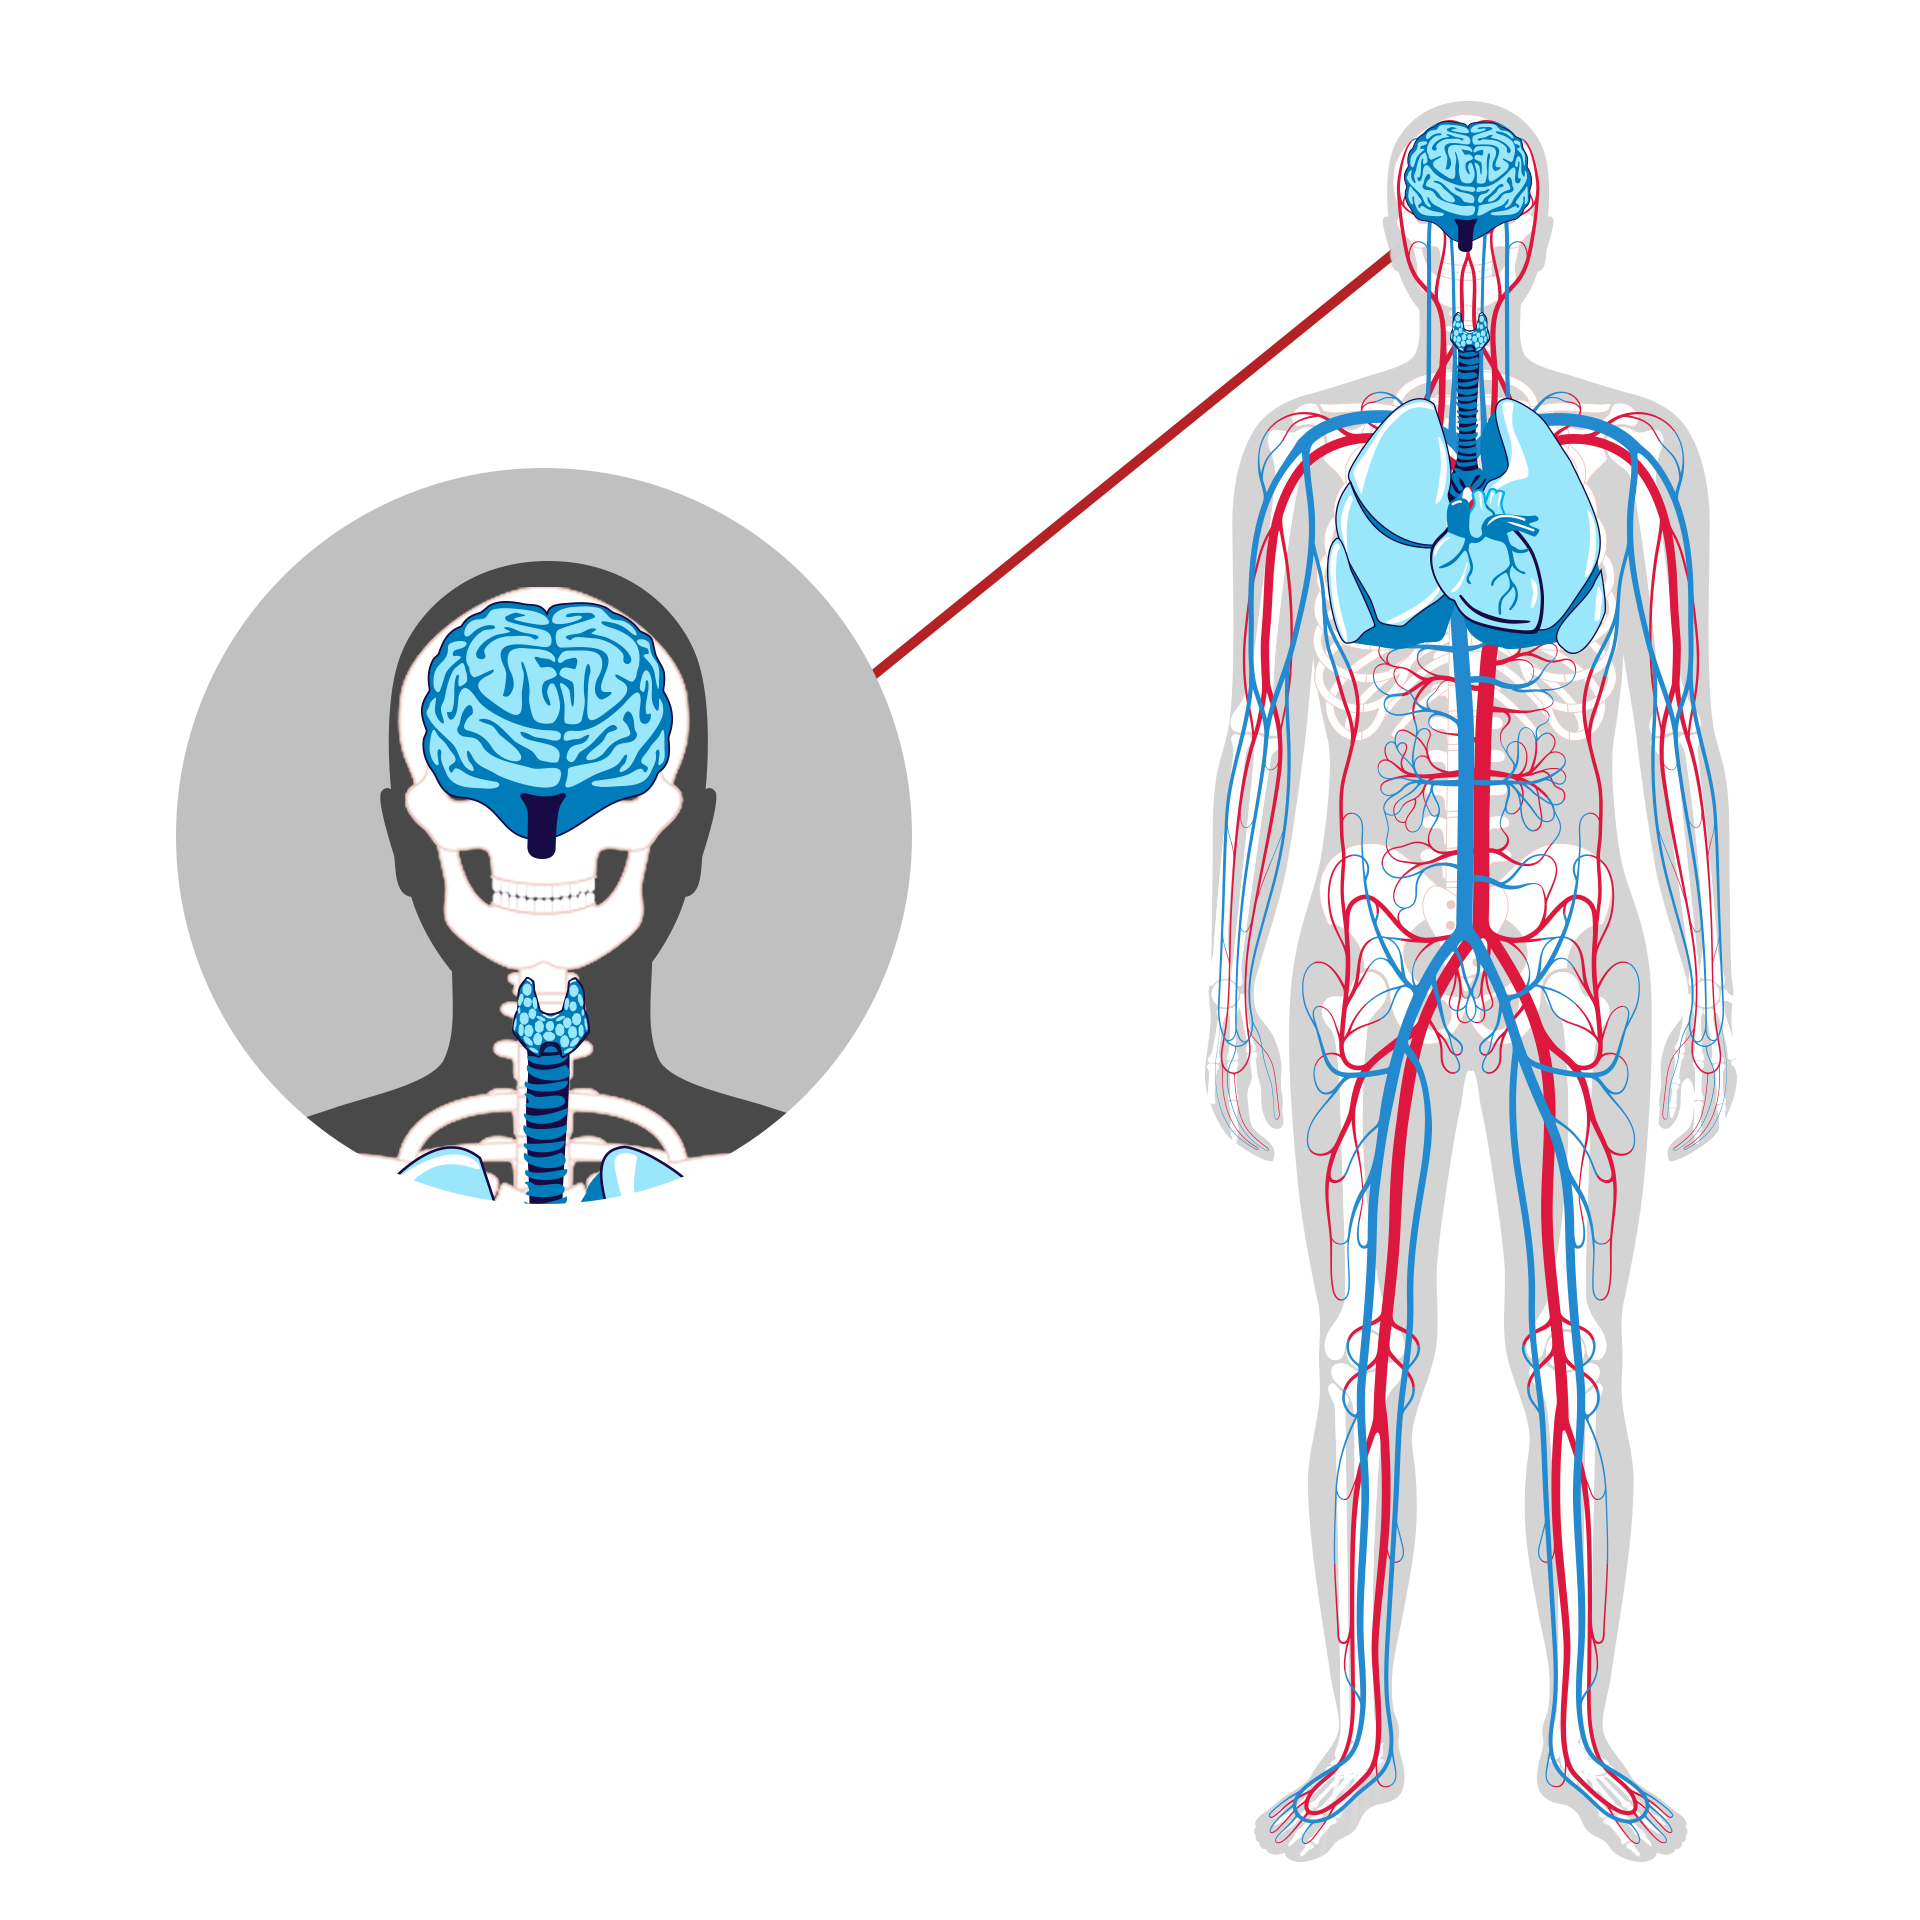

AREAS OF STUDY

TGB actively broadens our pre-clinical testing initiatives to assess the therapeutic potential of our products across a diverse spectrum of conditions, with primary focus on the brain, lungs and central nervous/inflammatory system(s). Our unwavering commitment to rigorous research positions us at the forefront of innovative therapies in this theater of study.